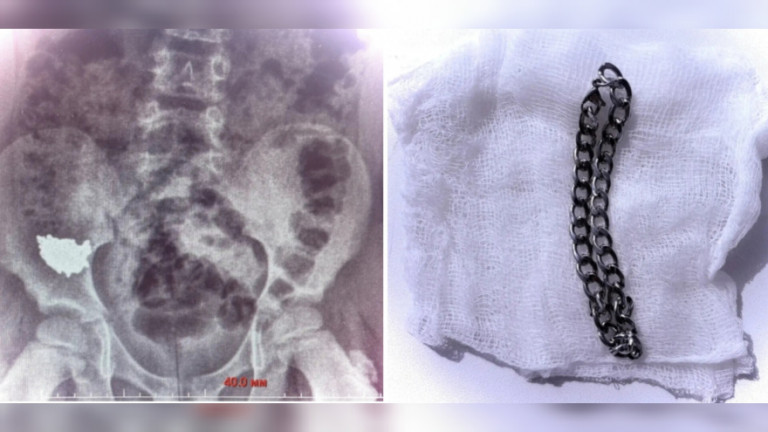

20 см металла в желудке: школьник в Воронеже проглотил цепочку

Во вторник, 7 апреля, министерство здравоохранения Воронежской области сообщило о случае с школьником, который во время игры проглотил 20‑сантиметровую цепочку. Родители…